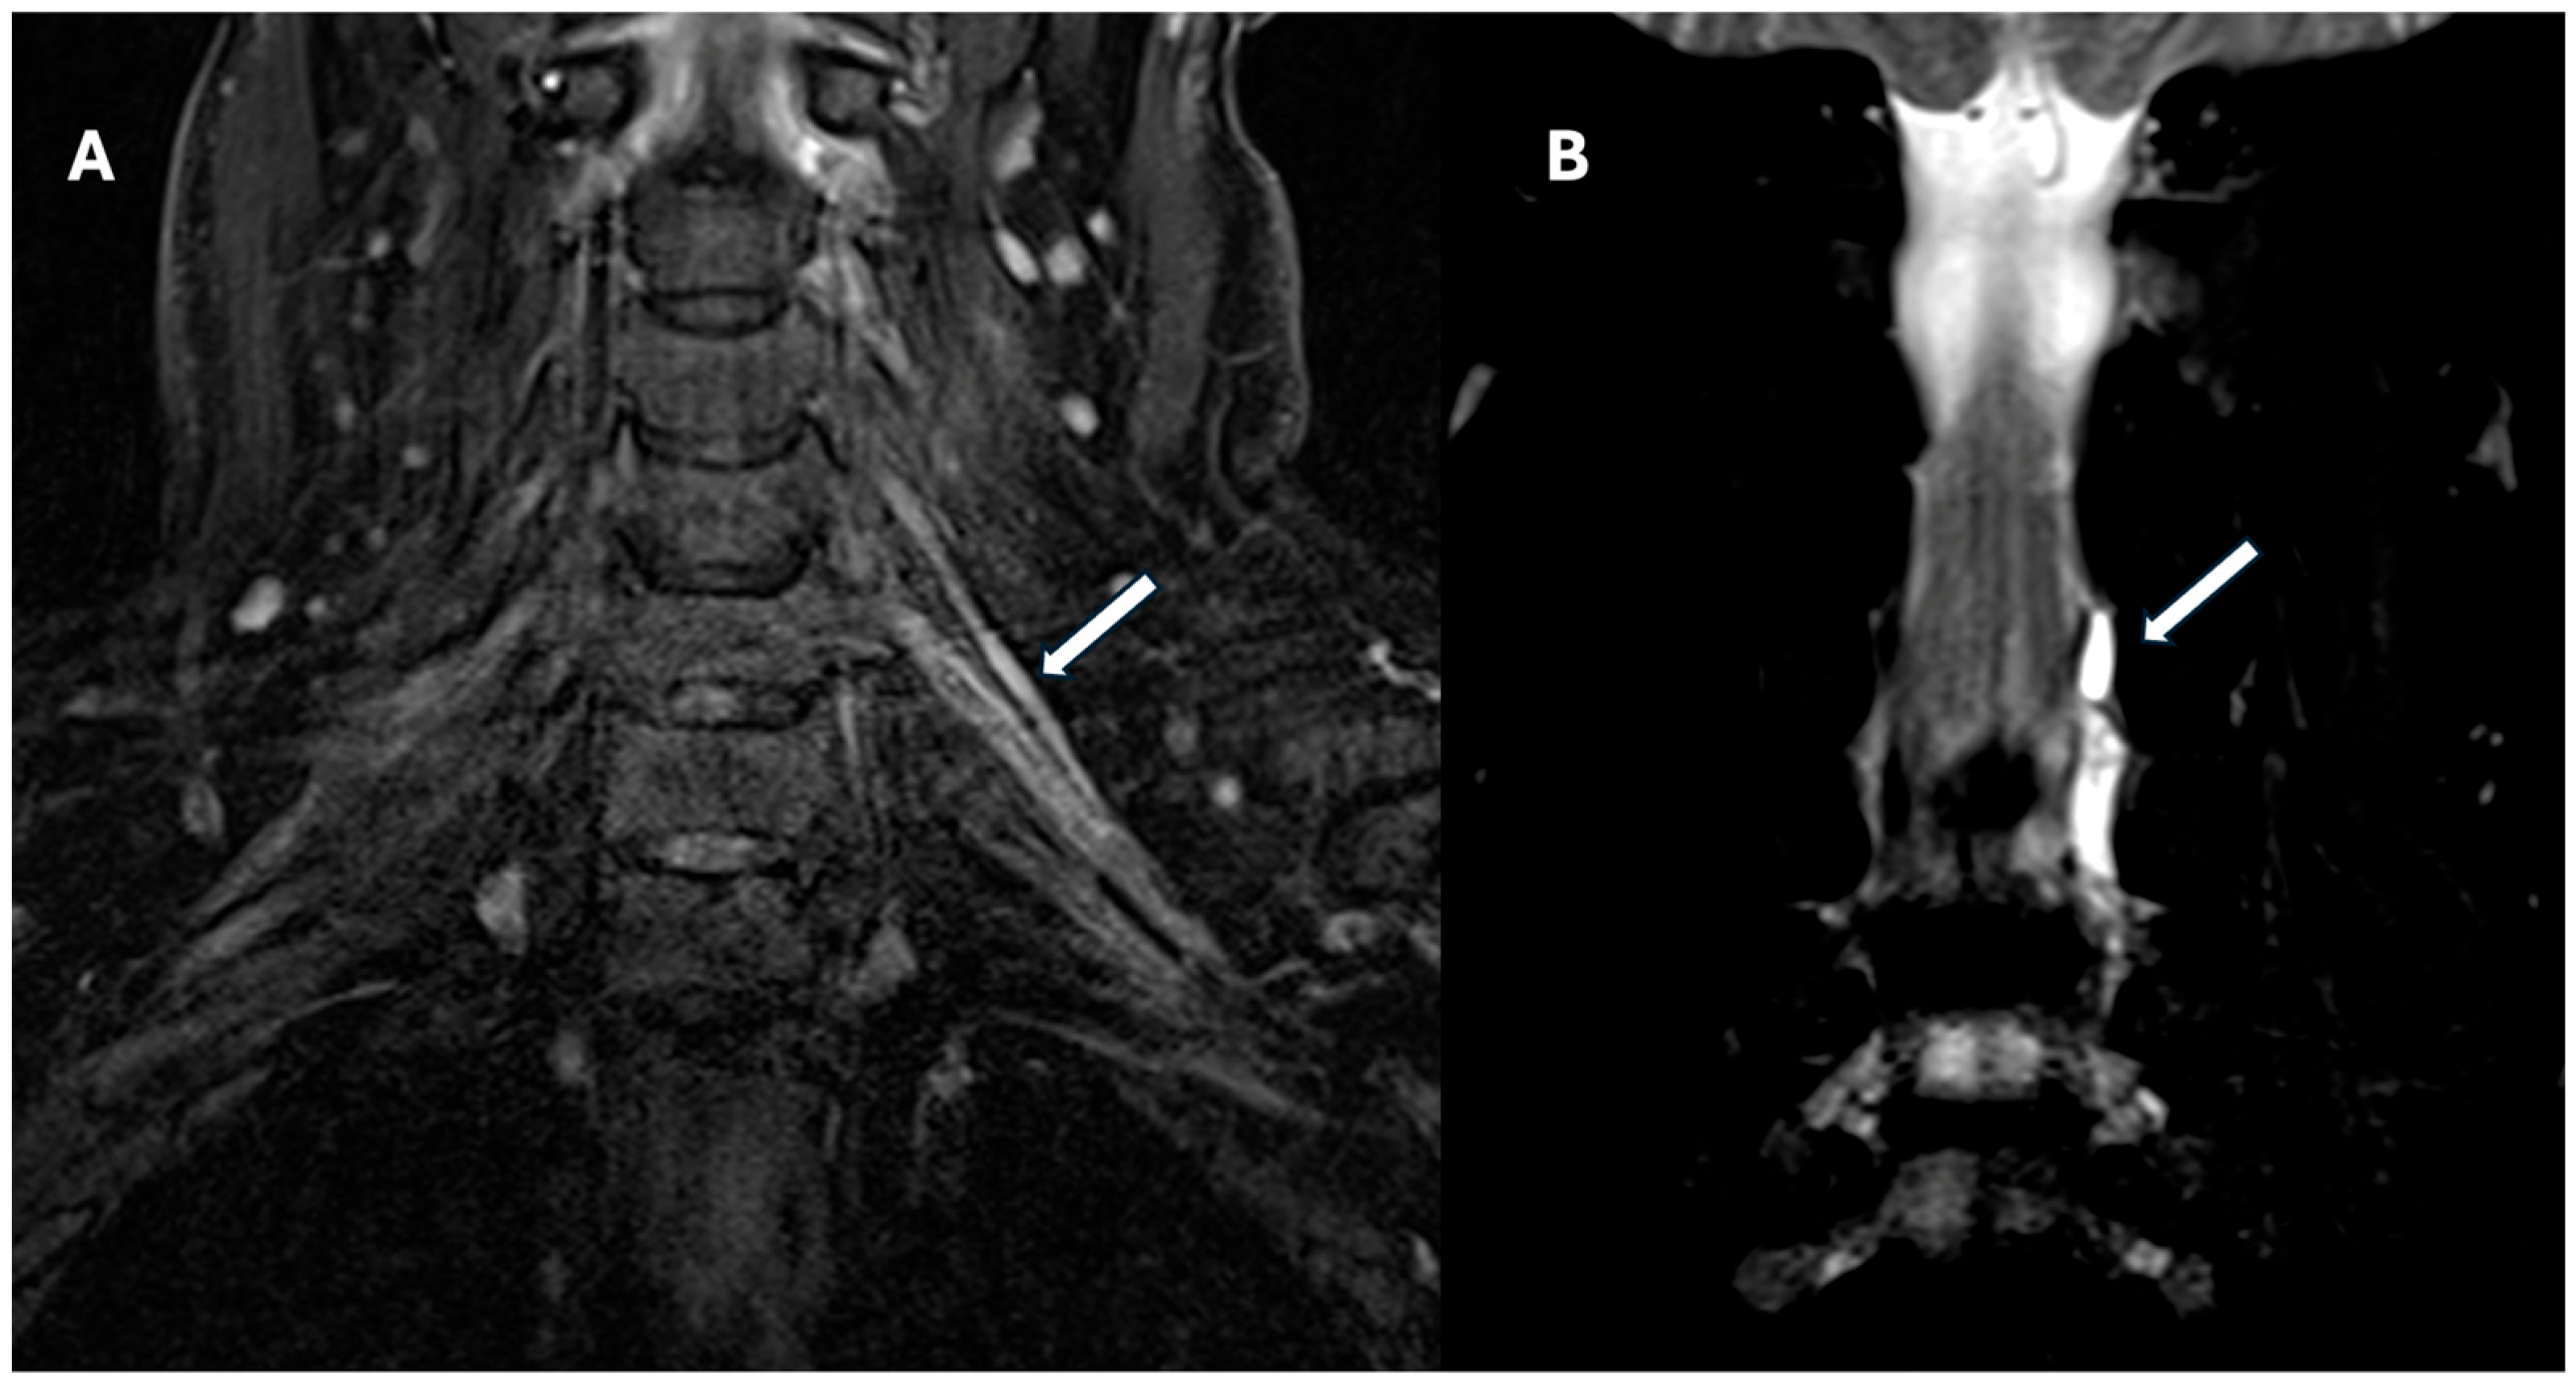

4.2. Magnetic Resonance Imaging (MRI)

- Yoshikawa, T.; Hayashi, N.; Yamamoto, S.; Tajiri, Y.; Yoshioka, N.; Masumoto, T.; Mori, H.; Abe, O.; Aoki, S.; Ohtomo, K. Brachial plexus injury: Clinical manifestations, conventional imaging findings, and the latest imaging techniques. Radiographics 2006, 26, S133–S143. [Google Scholar] [CrossRef]

- Felisaz, P.F.; Napolitano, A.; Terrani, S.; Parisi, C.; Toto-Brocchi, M.; Cè, M.; Alessandrino, F.; Oliva, G.; Cellina, M.; Gerevini, S. An Optimized 1.5 Tesla MRI Protocol of the Brachial Plexus. Neuroradiol. J. 2024, 37, 43–53. [Google Scholar] [CrossRef]

- Kwee, R.M.; Chhabra, A.; Wang, K.C.; Marker, D.R.; Carrino, J.A. Accuracy of MRI in Diagnosing Peripheral Nerve Disease: A Systematic Review of the Literature. Am. J. Roentgenol. 2014, 203, 1303–1309. [Google Scholar] [CrossRef]

- Brun-Vergara, M.L.; Reda, A.; Puac-Polanco, P.; Zakhari, N.; Shah, V.; Torres, C.H. MR Imaging of the Brachial Plexus: A Practical Review. Magn. Reson. Imaging Clin. N. Am. 2025, 33, 331–350. [Google Scholar] [CrossRef] [PubMed]

| Coronal 3D STIR | ~350 | 3000/194 | Multiplanar reformats, global plexus trajectory. | Ensure robust and uniform fat suppression; useful for MIP reconstructions; motion artifacts can degrade quality. |

| Coronal T1-weighted | ~320 | 647/6 | Defines fat planes, anatomical borders, mass encasement. | Good for anatomical landmarks and fat infiltration; align with STIR for nerve-to-fat contrast correlation. |

| Axial STIR | ~200 | Variable | Targets C5–T1 roots & cords; detects edema, denervation. | Small FOV boosts spatial resolution; watch for magic angle effect near oblique fibers. |

| Preganglionic Trauma | Limited utility; deep root visualization is challenging | Pseudomeningoceles, root avulsion, spinal cord signal changes (edema, hemorrhage); root separation | Enhancement of intradural root stumps; better delineation of avulsed roots | Pseudomeningoceles (not pathognomonic), paraspinal muscle atrophy, most common at T1 root |

| Postganglionic Trauma | Swelling, discontinuity, neuroma, segmental enlargement, hourglass constrictions; highly sensitive for terminal branches | Thickened nerves, high T2 signal, neuroma-in-continuity, muscle denervation | May enhance neuromas and detect perineural fibrosis | Denervation in target muscles, correlation with EMG, useful for surgical planning |